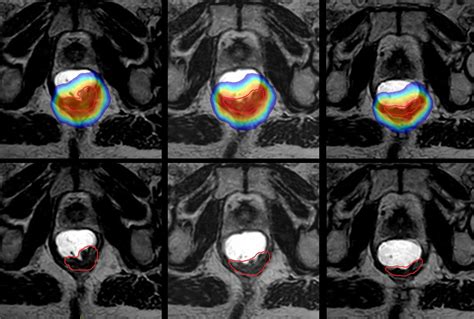

Why is lateralization so important in medical reports? Precision prevents medical errors and ensures that the correct tissue is being treated. For example, in radiation therapy, the delivery of high-energy beams must be perfectly calibrated to the "Rt" side to spare the healthy tissues on the opposite side. Surgeons also rely on this data to plan their incisions and lymph node dissections.

Advances in precision medicine allow doctors to look beyond just the "Right" or "Left" designation. They now use molecular profiling to understand the biology of the tumor. While the anatomical location tells the surgeon where to operate, the molecular profile tells the oncologist which targeted therapies will be most effective. Both pieces of information work together to form a comprehensive care plan tailored to your specific needs.

Modern imaging, such as PET-CT scans and MRIs, is the primary reason why we can be so specific about identifying Cancer At Rt. These technologies provide high-resolution images that allow radiologists to pinpoint the exact coordinates of a malignancy. When you review your scan results, look for these markers:

• Coordinates: Precise measurements of the mass's position within the organ.

• Involvement of Adjacent Structures: Whether the cancer has extended beyond the right-side boundary.